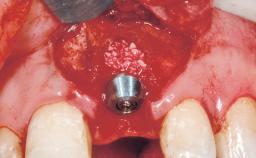

This 43-year-old male patient, a non-smoker, came to our practice because of a fracture of tooth 12 caused by a bicycle accident. Due to the combined para- and infrabony crown and root fracture, tooth extraction, and subsequent implant placement were suggested to the patient as the therapy of choice. The patient had high esthetic expectations with regard to the treatment outcome and asked for an immediate fixed provisional restoration. His individual esthetic risk profile summed up to a medium esthetic risk.

Placement Protocol Immediate implant placement

Socket Morphology Single-root socket

Socket Integrity Sufficient, with intact bone walls

Bone Volume Sufficient, with intact walls